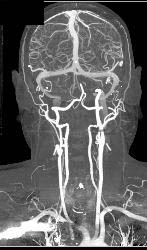

Ectatic Carotid Arteries in Loeys-Dietz Syndrome. Patient Also Has Stenosis to Origin of Left Subclavian Artery